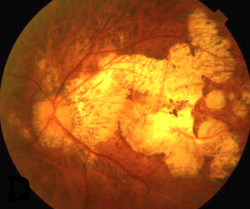

De los 142 ojos con miopía elevada, 23% tuvieron un disco grande, 18% un disco pequeño, y 39% tenían un disco inclinado. Los discos grandes tenían una mayor excavación papilar y una relación de inclinación superior; los discos pequeño tenían una excavación papilar más pequeña y una relación de inclinación inferior. Entre las características asociadas con alta miopía se incluyen un área más pequeña de anillo neurorretiniano, una mayor excavación papilar y una relación de inclinación inferior. La refracción, la excavación papilar, el área del anillo neurorretiniano, y la relación de inclinación se asociaron con defectos de Campo visual.

Este estudio encontró que los discos inclinados, grandes o pequeños eran frecuentes en ojos con miopía elevada. De estas características, sólo la inclinación del disco y la alta miopía por sí misma se asocian con la gravedad de la neuropatía óptica glaucomatosa.